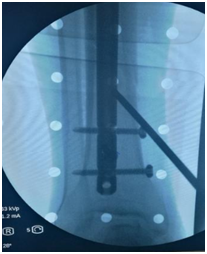

12、克氏针钩固定技术

对于前交叉韧带止点骨折,采用两枚克氏针钩进行固定,再于胫骨结节处用门形钉压住克氏针尾,可以起到比较好的固定作用。

17、克氏针内铰链技术

对于外翻型后外侧旋转不稳的损伤,外侧副韧带尺侧束的损伤一期修复后仍然不稳的,可运用克氏针内铰链技术来增加稳定性。